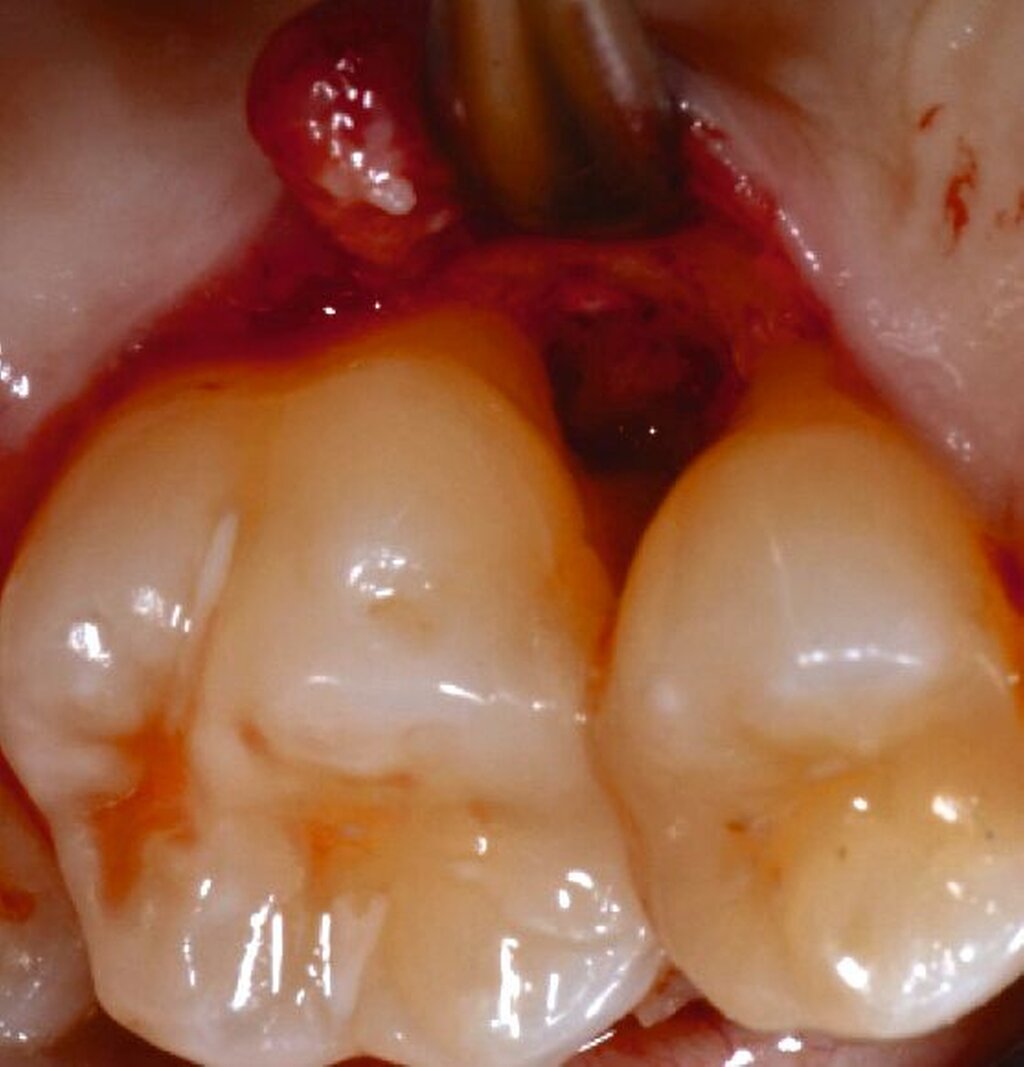

Fall 1 – einfach

Fall 2 – fortgeschritten

Fall 3 – komplex